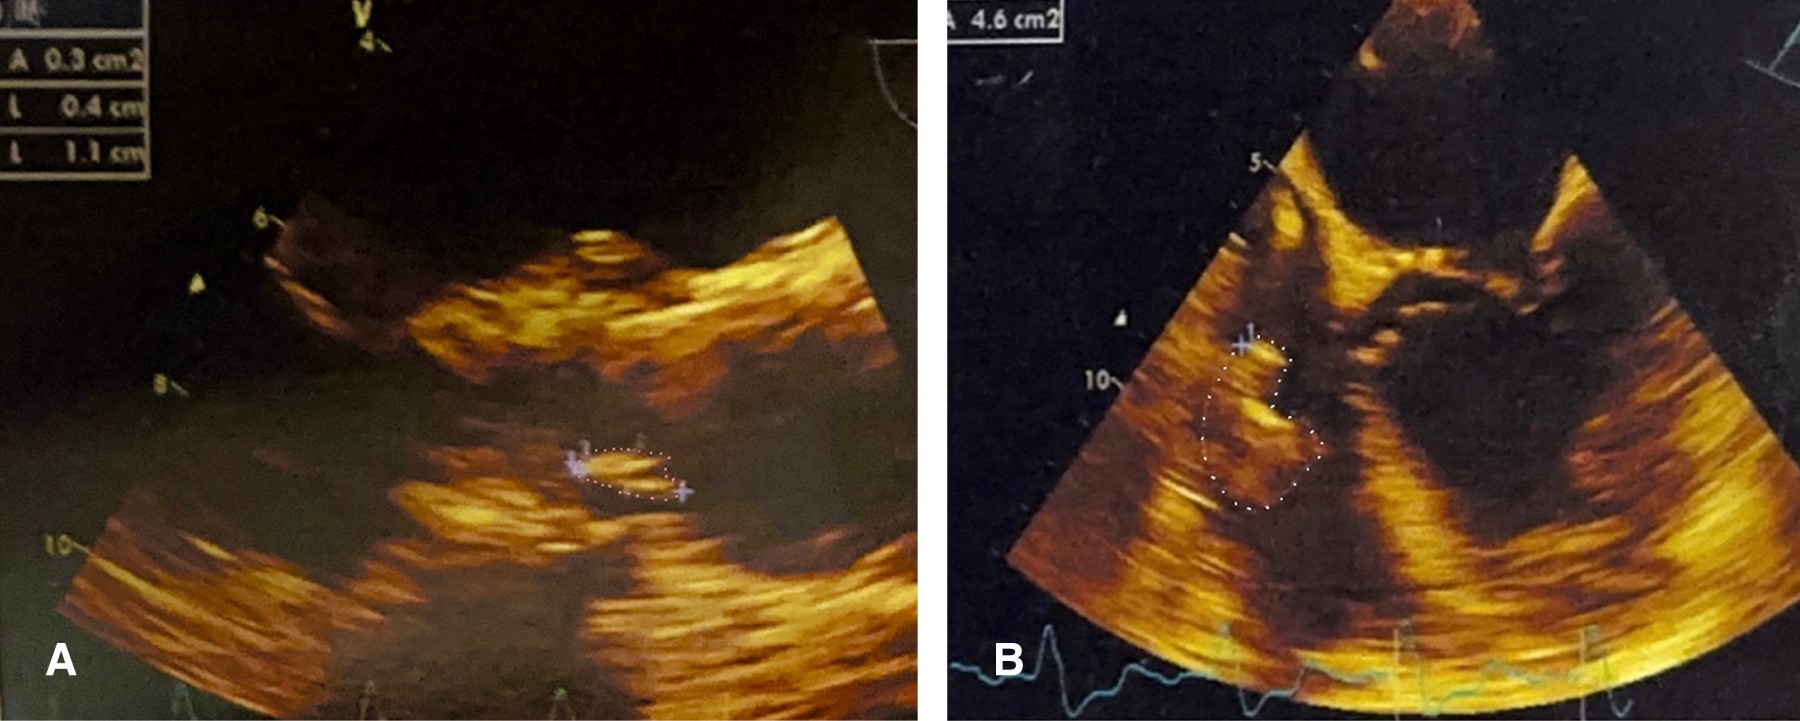

Figura 1

Figura 2